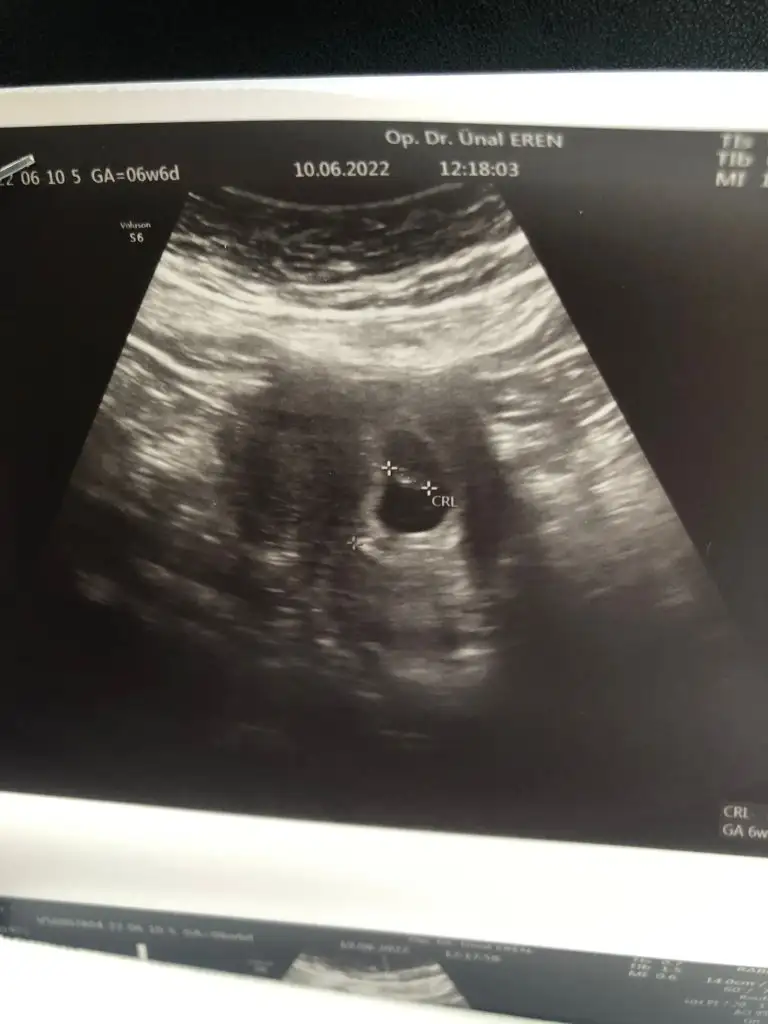

5 ve 14. haftaya kadar olan ultrason fotolarınızı paylaşın. Vajinadan mı yoksa karından mı çekildiğini ve kaç haftalık olduğunu da mutlaka belirtin.

karından mıEki Görüntüle 3081825 7+5 haftalık bebek sağa yerleşmiş dedi doktorumuz bize de bakar mısınız?